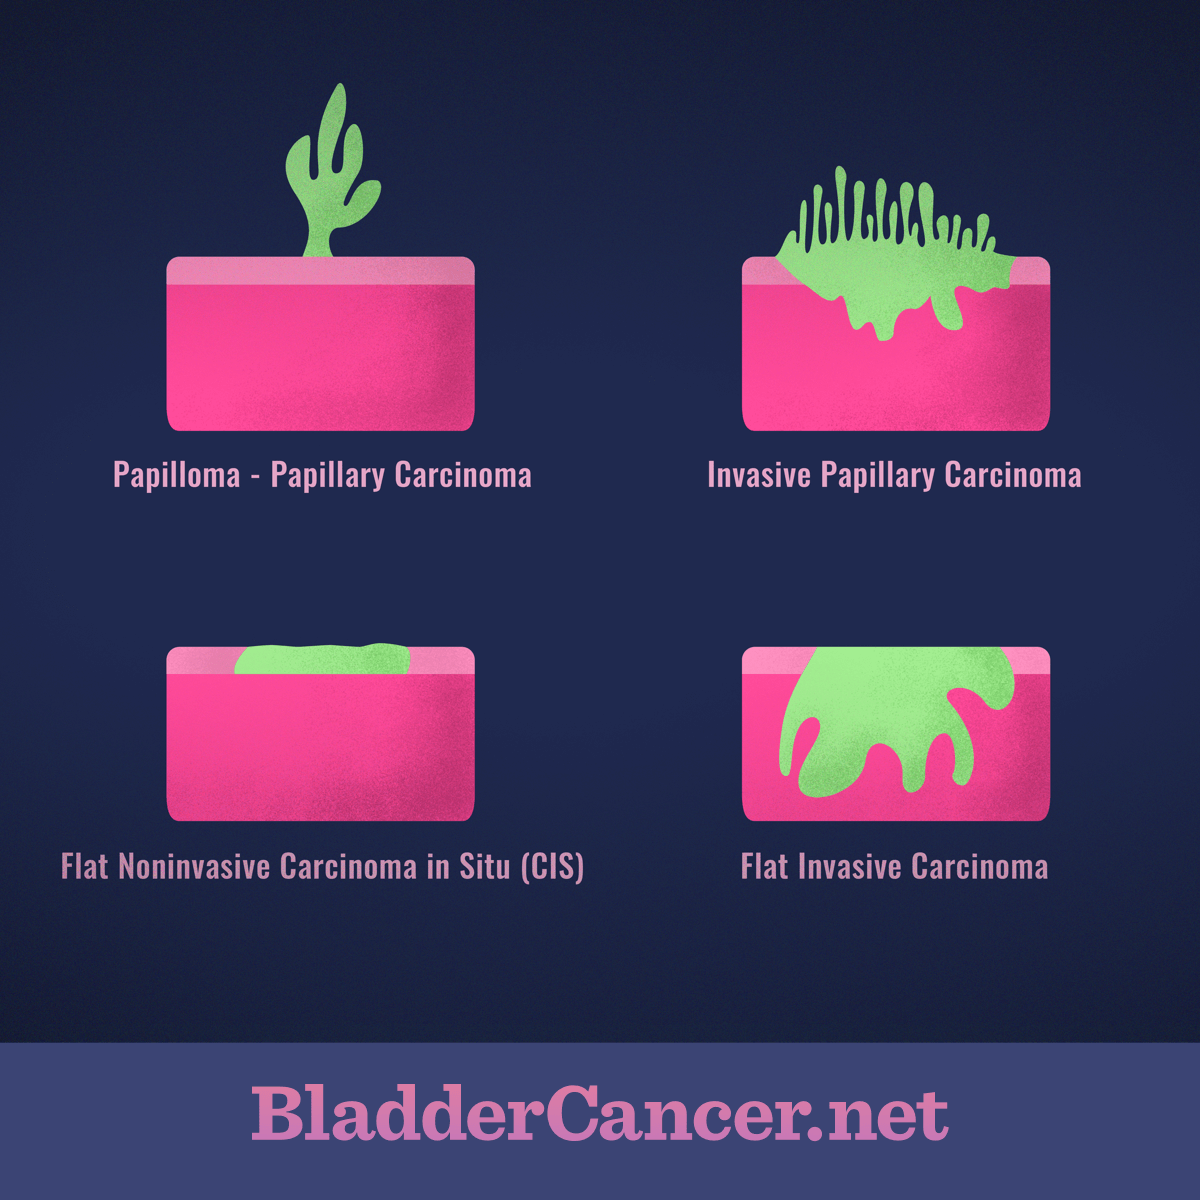

Classification Of Bladder Tumors : TNM stage classification of bladder …

Understanding the Different Types and Forms of Bladder Cancer

Overview of staging and grading of bladder cancer tumor. The figure was …

Classification Of Bladder Tumors : TNM stage classification of bladder …

Update on Bladder Cancer for the Practicing Pathologist

Bladder Cancer Pathology – Net Health Book